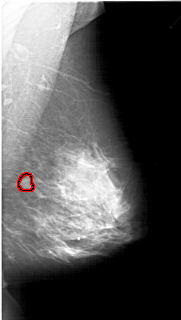

A_1218_1.RIGHT_MLO

RIGHT_MLO LINES 6076 PIXELS_PER_LINE 3436 BITS_PER_PIXEL 12 RESOLUTION 43.5 OVERLAY

FILE: A_1218_1.RIGHT_MLO.OVERLAY

TOTAL_ABNORMALITIES 1

ABNORMALITY 1

LESION_TYPE MASS SHAPE LOBULATED MARGINS ILL_DEFINED

ASSESSMENT 4

SUBTLETY 2

PATHOLOGY MALIGNANT

TOTAL_OUTLINES 1

BOUNDARY